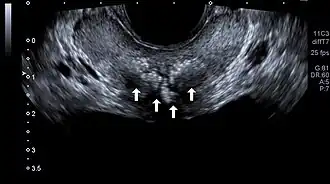

| Transrectal ultrasound of prostatic stones in the peri-urethral zone of the prostate | |

Prostatic calculi (PC), prostatic stones, prostatic calcification or prostatic lithiasis, are hyper-echoic mineral deposits in the prostate that are frequently detected incidentally during transabdominal ultrasonography, transrectal ultrasonography, or computed tomography.[1][2][3]